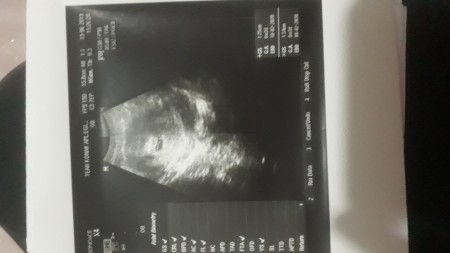

Kese var bebek var kalp atışı yok. çünkü adet tarihiniz doğru olsa 15 haziranda yaptığınız testte. Haftada ultrasyon girdim kese vardi bebeğin kalp atışını goremedi dokdor bugün gittiğimde yine karnımdan ultrasyon da bakıldı ve kalp atışı yok dendi renkli ultrasyon girmem istendi boş gebelik ten şuphelendi sizce ne olabilir. Xxbrnxx 8y 6y 28 06 13. Mrblar ben 7 artı 5 günlük hamileyim lekelenmem var doktora gittiğimizde 2 hafta geriden geliyor dedi kesem bebeğim var ama kalp atışı yok 1 hafta sonra gel çok umitlenme dedi duyamassak kürtaj dedi bu.

Kese 7 haftalık bebek 5 haftalık ama henüz kalp atışı yok doktor vajinal muayene etti ve kalp atışı olmadığı için sağlıklı bi bebek değil dedi iler ki haftalar da kalp atışının olması münkün mü bu durumu yaşayan yada bilgi sahibi olan varsa bana bilgi verebilir mi. Kese var oluşum güzel denildi doktor tarafından. 7 hafta 5 günlük gebelikte bebeğin ve kalp atışının rahatlıkla görülebilmesi gerekir ancak sanırım sizin adet tarihiniz yanıltıyor geç yumurtlama olmuş olabilir. Kese var ama bebek yok 28 yaşındayım 21 aylık evliyim.

Yahu kalp atışı olmazsa alınacağını bizde bilioz. Kese var ama kalp atisi yok. Kadarlık ki hemen umutsuz olma zaten ilk kese görünür benmde görünmemişti bos gebelik demişlerdi 3 gün sonra kalp atışı bile görüldü çok şükür bazende duruş pozisyonuyla alakalı görünmüyo. Kese var bebek yok.

Kese var bebek ve kalp atisi yok. Bebeğin kalbinin atışları 5. Arkadaşlar 7 haftalık hamileyim bugün doktora gittim kese var ama kalp atışı yok haftaya gel kürtaj yapalım dedi çok korkuyorum ne yapmaliyim. 2 yıl önce gebelik kategorisinde yasmin sordu.